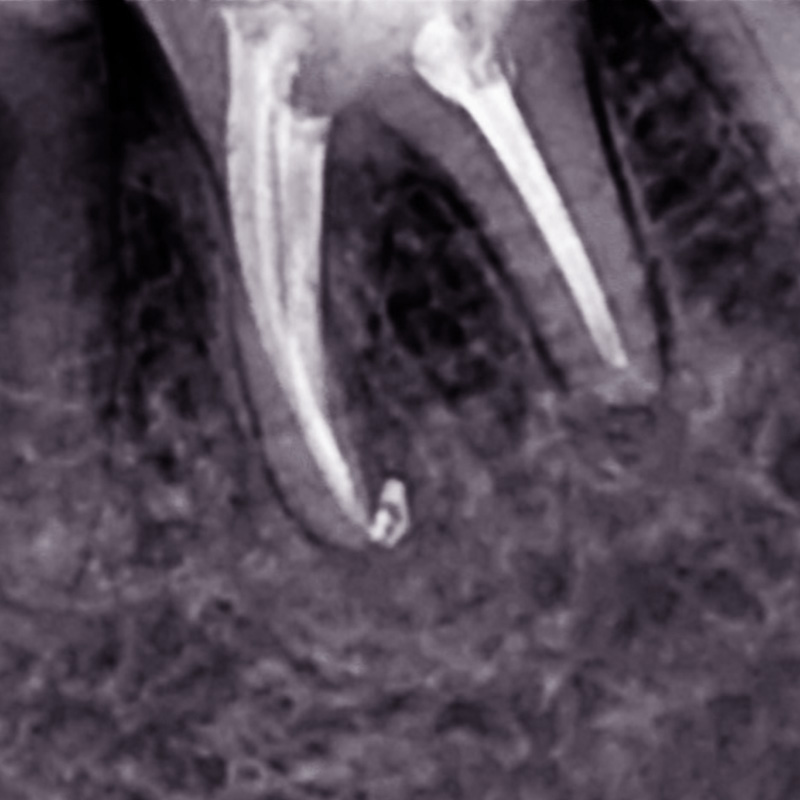

Лечение хронического фиброзного пульпита 13 зубаСмотреть работуСрок лечения:2 часа (2 посещения)Сумма лечения:15 350 руб.